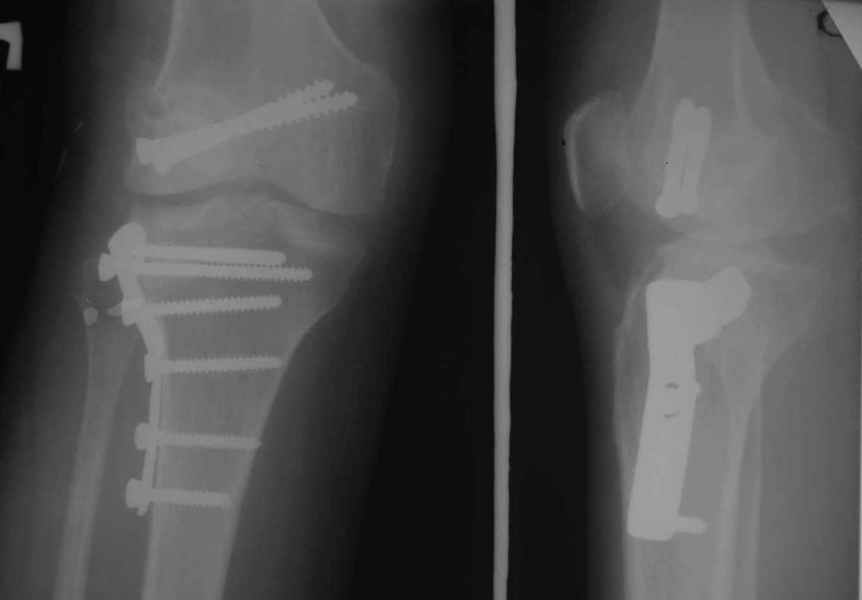

Уважаемые коллеги!На прием обратилась больная 38 лет. Травма 17.01.2005. 23.01.2005 - операция в одном из стационаров области - остеосинтез мыщелка бедра винтами, Остосинтез мыщелка большеберцовой кости L-образной пластиной.

Остальные снимки Ноябрь 2005

Уважаемый Евгений ! Спасибо за ответ, но мне представляется, что в нашем случае основной проблемой является не столько прогрессирующий вальгус конечности, сколько несросшийся перелом мыщелка бедра и дефект мыщелка большеберцой кости - вероятно первичная репозиция выполнялась без пластики.

Относительно "рубцовой подушки" я имел в виду остатки мениска ( частично вколоченного в дефект мыщелка и фрагменты хряща), все таки на рентгенограммах суставная щель в этом отделе чем то заполнена. Что касается некроза мыщелка бедра, то мне кажется он уже наступил - томограмма ноябрь5.

С учетом всего сказанного - наличия прогессирующего вальгуса конечности, довольно приличного объема движений, имеющегося, вероятно, некроза мыщелка бедра, наиболее рациональным представляется удалить пластину с б\б кости, произвести остеотомию б\б кости с коррекцией вальгуса, разгрузив тем самым наружный отдел сустава, и синтезировать фрагменты голени накостным фиксатором. Максимально тано начать восстановление движений в суставе. Скорее всего рано или поздно речь о протезировании всеже возникнет, но мы хотя бы будем иметь приличную ось конечности.